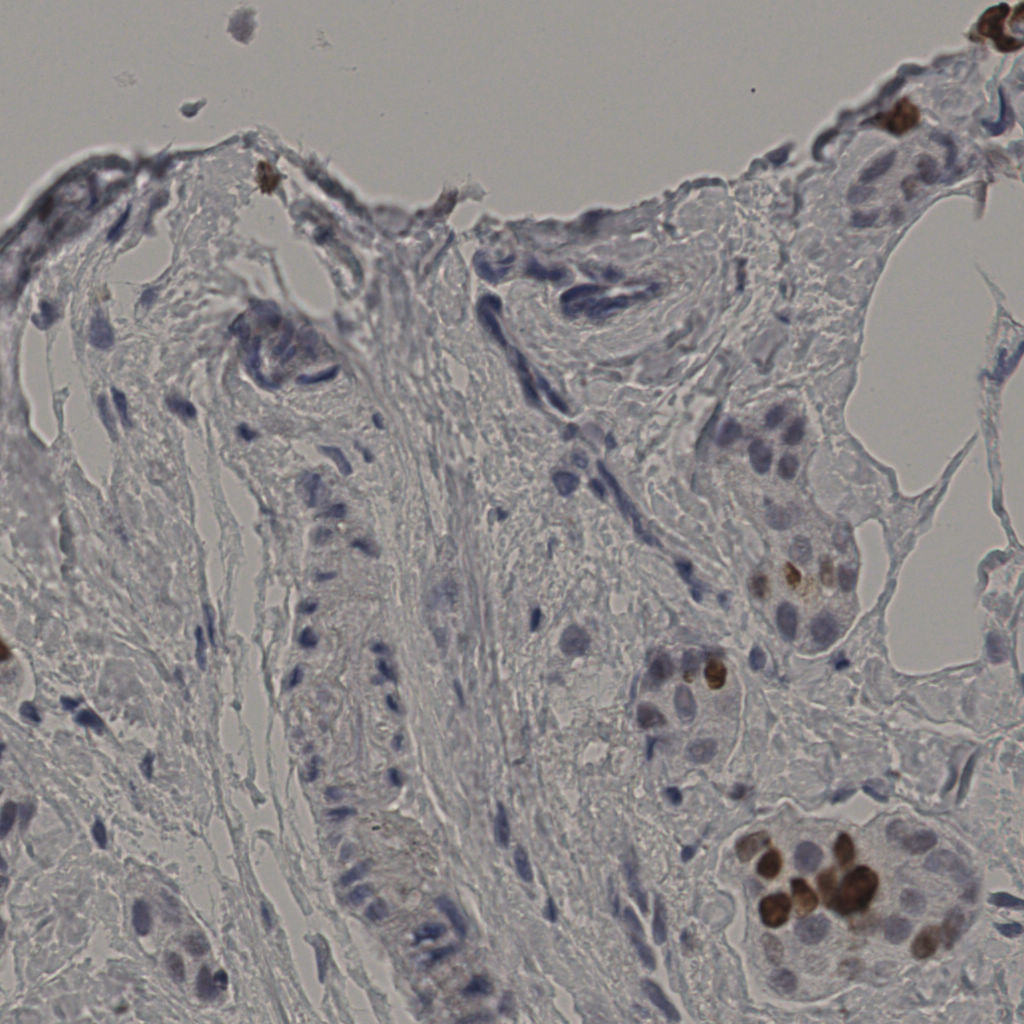

缩略图

标记后

标记前